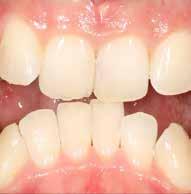

Általánosan elmondhatjuk, hogy a fogszabályozó kezelés iránt érdeklődő páciensek az első konzultáció során elsősorban az esztétikai kívánalmaiknak adnak hangot, és ritka az olyan eset, amikor a funkcionális problémák kerülnek előtérbe a részükről.

Nagyon fontos, hogy a modern arc- és mosolyesztétika által vezérelt fogszabályozási elvek alkalmazásával – minden esetben – az esztétikai céloknak megfelelően kerüljön megvalósításra az okklúziós korrekció.

A természetes mosoly tervezésénél az alábbi esztétikai paramétereket kell figyelembe vennünk:

1. A mosolyvonal megfelelő íves lefutása;

2. A felső metszőfogak teljes vertikális láthatósága;

3. Az íny ideális láthatósága (hölgyeknél 1-2 mm, férfiaknál 0-1 mm);

4. A felső fogív megfelelő szélessége. A cél a 10 vagy 12 fogas mosoly, második premoláristól második premolárisig, vagy első nagyőrlőtől első nagyőrlőig;

5. A felső középső metszők antero-posterior pozíciója a felső

A 28 éves hölgypáciens is elsősorban a szép mosoly elérésének igénye miatt szeretett volna fogszabályozást, bár tudomása volt a mélyharapásáról (1–5. képek).

A kezelési célokat a fogívek tágítása a megfelelő mosolyszélességhez és az alsó frontfogak torlódásának feloldásához, valamint a mélyharapás és a kismértékű disztálharapás korrekciója jelentették (6–11. képek).

Passzív önligírozó fix fogszabá-

lyozó készülékkel 15 hónapig tartott a kezelése. Az ilyen mélyharapásos esetekben nagyon fontos, hogy a harapásemelésnél nem történik intrúzió a felső fogíven, mert az kifejezetten negatívan befolyásolná a vertikális mosoly-display-t! A fogszabályozó kezelés után, ahogy az általában lenni szokott, a bölcsességfogak eltávolításra kerültek. Mint minden esetben, a fogszabályozás aktív fázisa után a retenció, a passzív helyben tartó fázis a kezelési eredmény megtartásához rendkívül fontos!